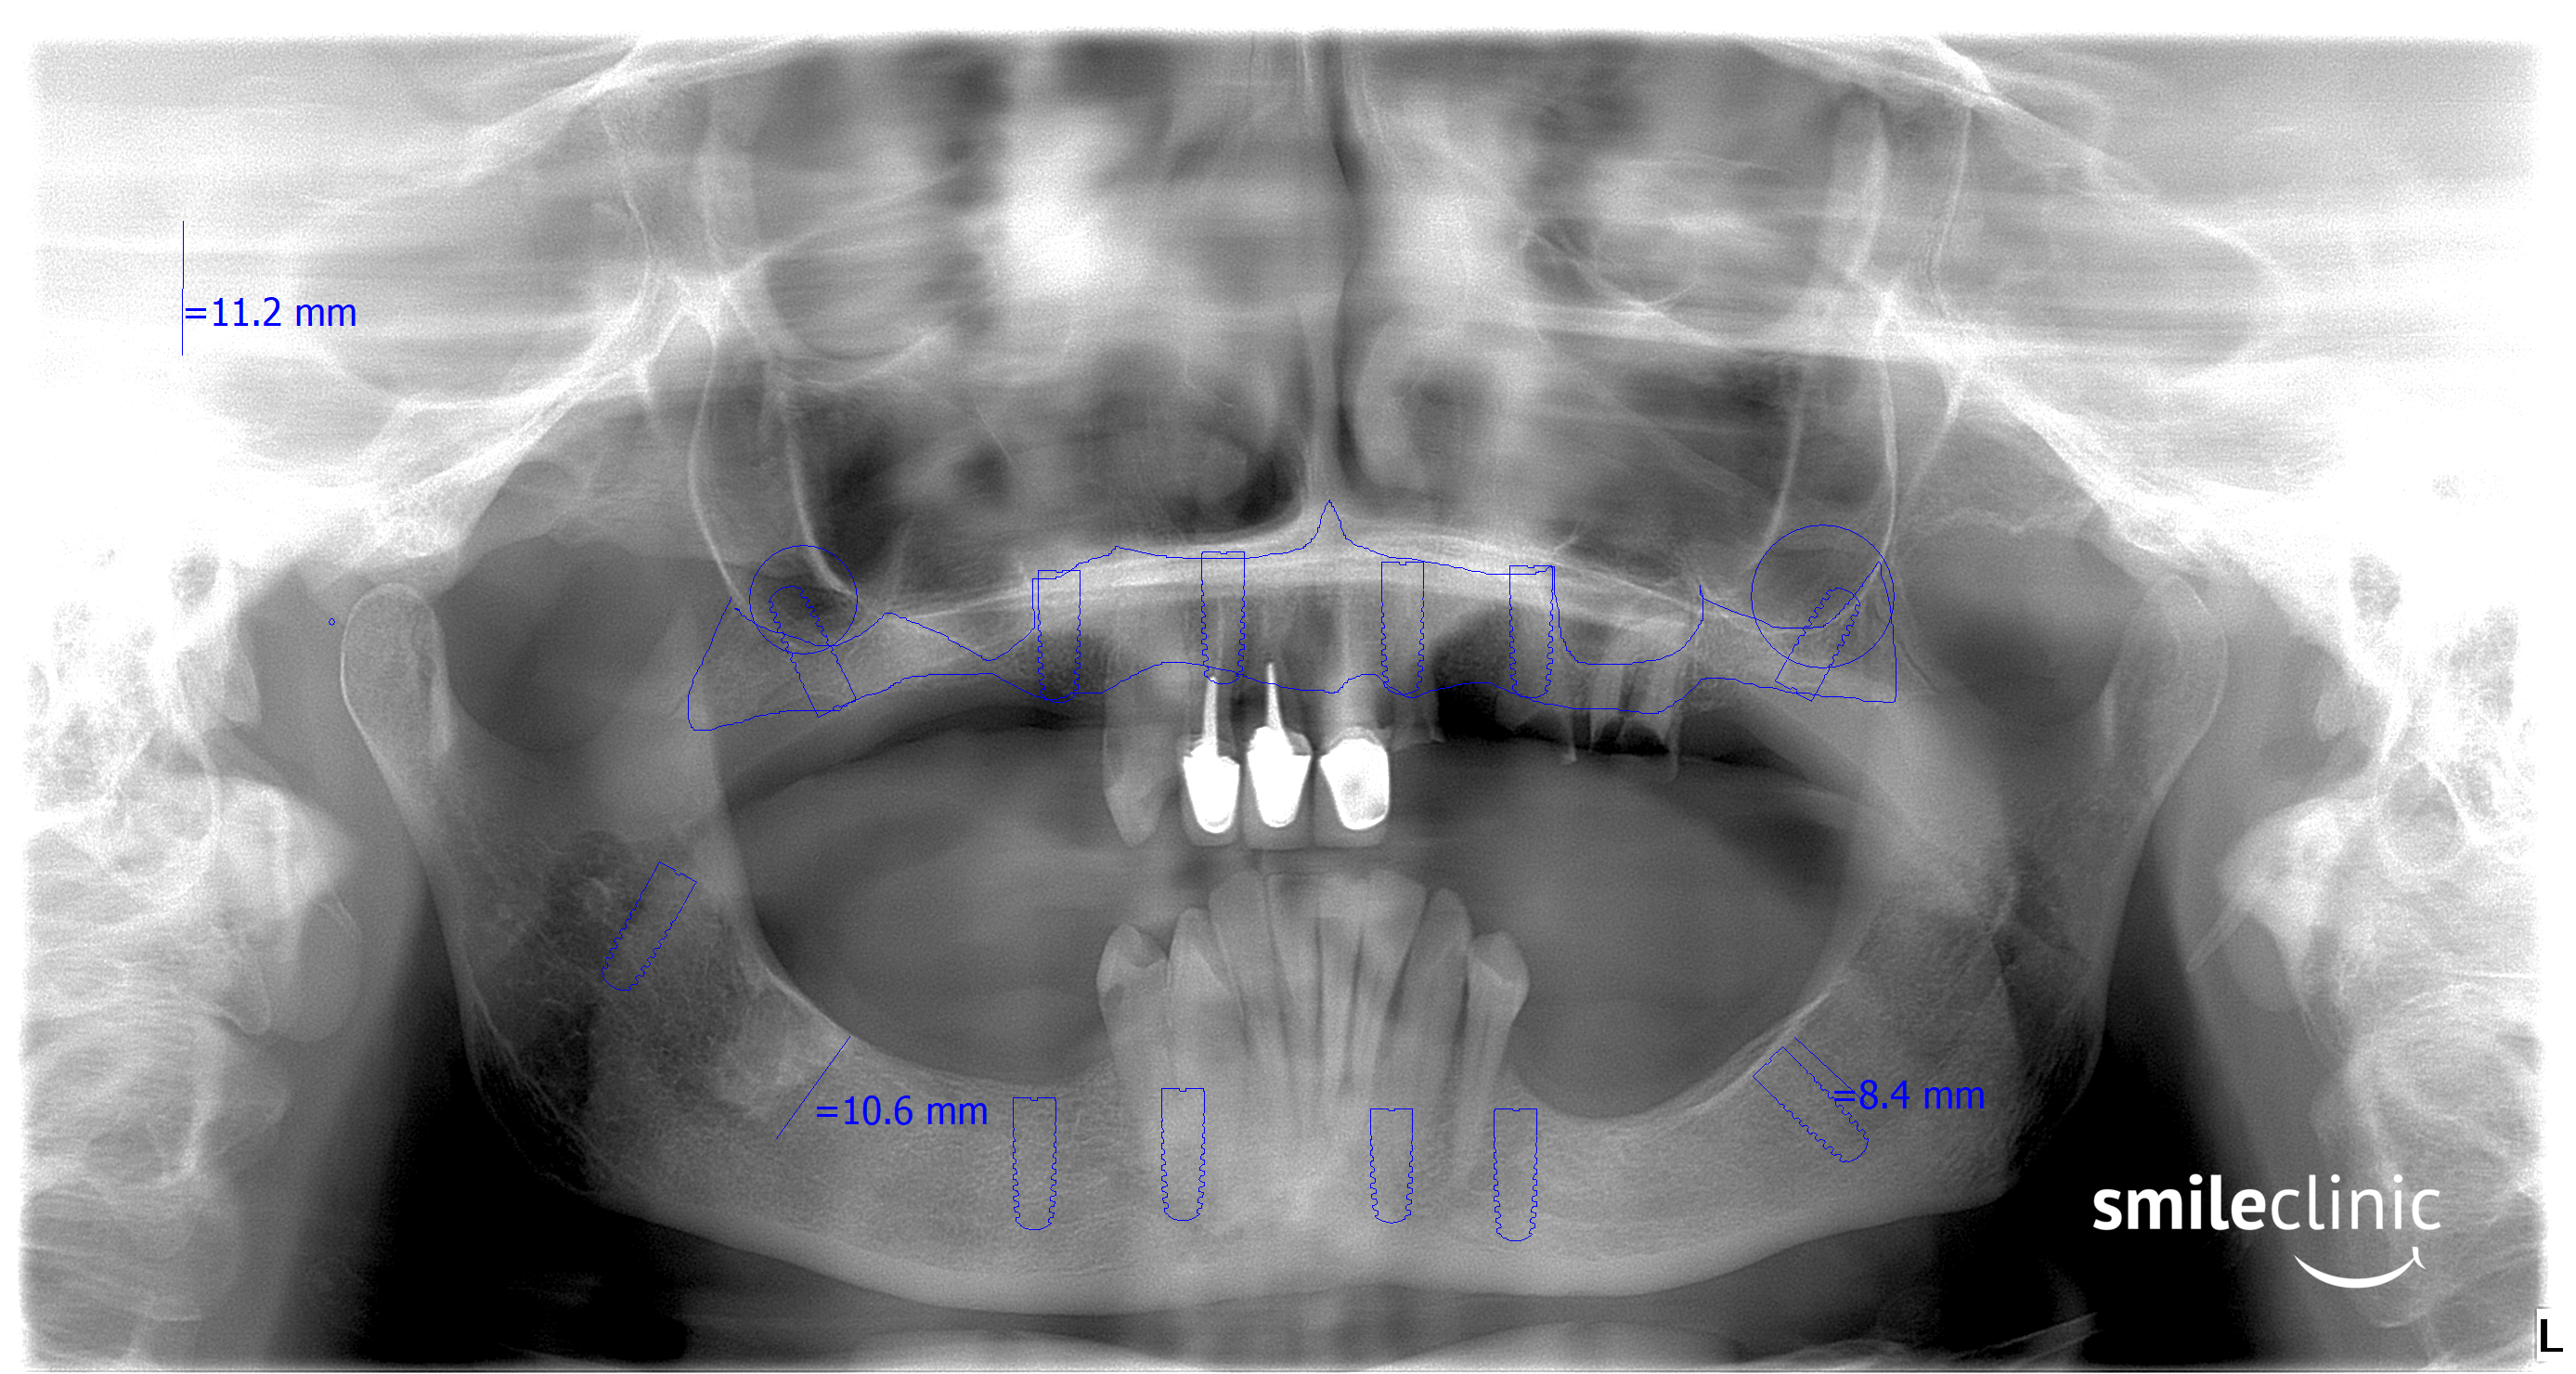

This patient recieved All on 5 procedure on both her jaws. As you can see in the X-ray taken after the treatment, she now has 5 dental implants in her lower and 5 dental implants in her upper jaw. On these implants is placed a fixed 14-point bridge.